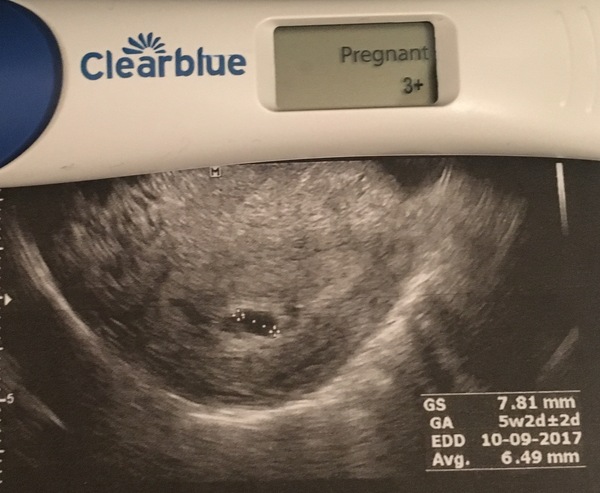

Here is the scan from today- there's just nothing there so hoping this won't upset anybody. Test is also from today- hcg must be high no matter what's happening

(Scan was transvaginal)